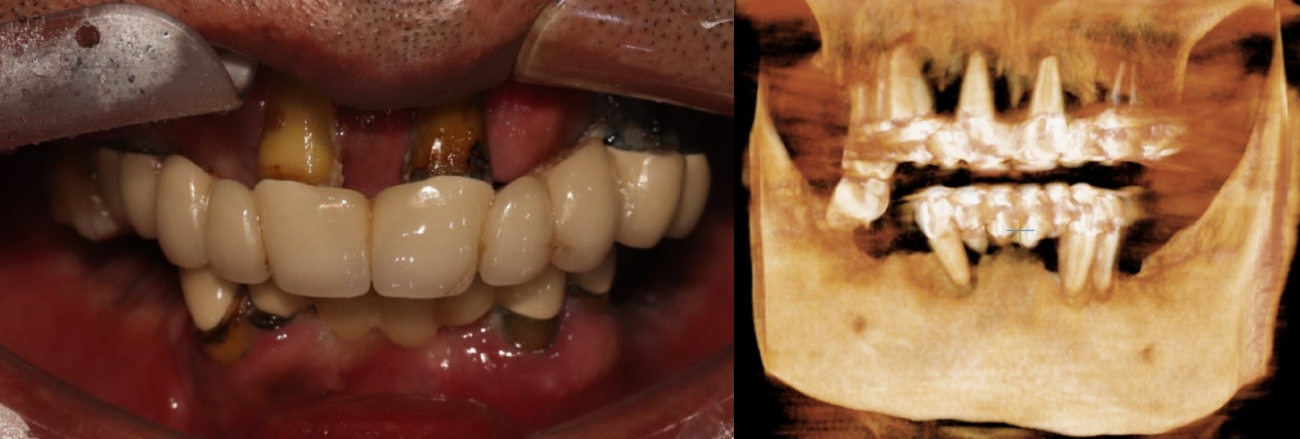

나이가 들면서 전체 치아가 흔들리거나 손상되어 발치 후 전체 임플란트(전악 임플란트)가 필요한 경우가 많아요. 특히 만 65세 이상 환자분들은 평생 1인당 2개까지 임플란트 건강보험 혜택이 적용되니 꼭 확인해 보세요! 이번 증례는 심각한 잇몸 질환으로 모든 치아를 상실한 60대 환자분께서 정교한 맞춤형 전악 임플란트를 통해 건 강한 미소와 저작 기능을 회복한 과정입니다. CASE. 60대 남성 환자, '전체 치아 흔들림'으로 내원 "전체 치아가 흔들리고 아파서 임플란트를 하고 싶어요." 여러 치과를 알아보시던 중, 지인의 소개로 저희 병원을 찾아주셨습니다. 처음부터 전악 임플란트를 염두에 두고, 풍부한 임상 경험을 가진 의료진을 찾고 계셨습니다. 정밀 진단 결과 구강 검진 및 CT 촬영 결과, 환자분의 상태는 매우 심각했습니다. * 구강 상태: 위아래 모든 치아가 심하게 흔들리고, 치아 뿌리가 노출될 정도로 잇몸 조직이 붕괴된 상태였습니다. * CT 및 파노라마 소견: 치아를 지지해야 할 잇몸뼈(치조골)가 염증으로 인해 대부분 소실되어, 치아들이 뼈 속에서 떠 있는 '부유치(floating tooth)' 상태였습니다. 자연치아를 최대한 보존하는 것이 원칙이지만, 이미 치아 뿌리 끝까지 염증이 퍼져 회복이 불가능했습니다. 환자분께 상태를 자세히 설명드린 후, 전체 발치 및 전악 임플란트 계획을 수립했습니다. ![]() ![]() 개인별 맞춤 치료 계획 환자분의 구강 구조와 심미성을 고려하여 아래와 같이 맞춤형 치료 계획을 세웠습니다. * 상악 (윗니): 6개의 임플란트 식립 후 '임플란트 지지 부분틀니 (IARPD)' 붕괴된 앞니 잇몸과 입술의 볼륨감을 심미적으로 회복시키기 위해, 어금니는 임플란트 고정성 보철로 단단히 잡아주고 앞니는 틀니의 잇몸 부분(flange)을 이용해 자연스러운 외모를 재현하는 방식입니다. * 하악 (아랫니): 8개의 임플란트 식립 후 전체 ‘고정성 보철' 전체 치아를 임플란트와 보철물로 단단하게 고정하여 본래 치아처럼 편안하게 사용하는 방식입니다. 치료 과정 1. 발치 및 잇몸 회복 모든 치아를 발치한 후, 염증이 완전히 사라지고 잇몸이 안정될 때까지 약 2개월간 기다렸습니다. 이 기간 동안 환자분의 식사와 심미성을 위해 임시 틀니를 제작해 드렸습니다. ![]() 2. 정확하고 안전한 임플란트 식립 - 상악수술: 잇몸뼈가 얇아 고난도 수술인 상악동 거상술을 동반하여, 계획된 위치에 정확하게 6개의 임플란트를 식립했습니다. 충분한 마취와 정교한 수술, 그리고 숙련된 봉합으로 환자분의 불편감을 최소화하고 빠른 회복을 유도했습니다. ![]() - 하악수술: 최종 보철물의 형태와 기능을 고려하여 적절한 간격과 위치에 8개의 임플란트를 완벽하게 식립했습니다. ![]() 3. 뼈 유착 및 2차 수술 임플란트가 뼈와 단단히 붙는 약 3~4개월 동안 임시 틀니를 사용하며 기다립니다. 이후 모든 임플란트의 ISQ 수치(임플란트 안정성 지수)가 양호한 것을 확인하고, 잇몸 밖으로 임플란트를 노출시키는 간단한 2차 수술을 진행했습니다. ![]() 4. 임시 보철 및 최종 보철 준비 현재는 최종 보철물을 올리기 전, 임시 보철물(PMMA)을 사용하여 환자분이 적응하는 단계를 거치고 있습니다. 임플란트가 완벽하게 식립되었기 때문에 성공적인 최종 결과가 기대됩니다. 전악 임플란트는 단순한 치아 보철을 넘어, 무너진 식생활과 자신감을 회복하는 중요한 치료입니다. 이백점치과는 최소한의 임플란트 식립으로 통증과 불편을 줄이면서도 안정적이고 심미적인 결과를 추구합니다. 풍부한 임상 경험과 높은 환자 만족도로 증명된 실력으로, 치아가 전혀 없는 분들도 다시 편안한 식사와 활짝 웃는삶을 되찾을 수 있습니다. 당신의 현명한 선택, 이백점치과와 함께하세요. |